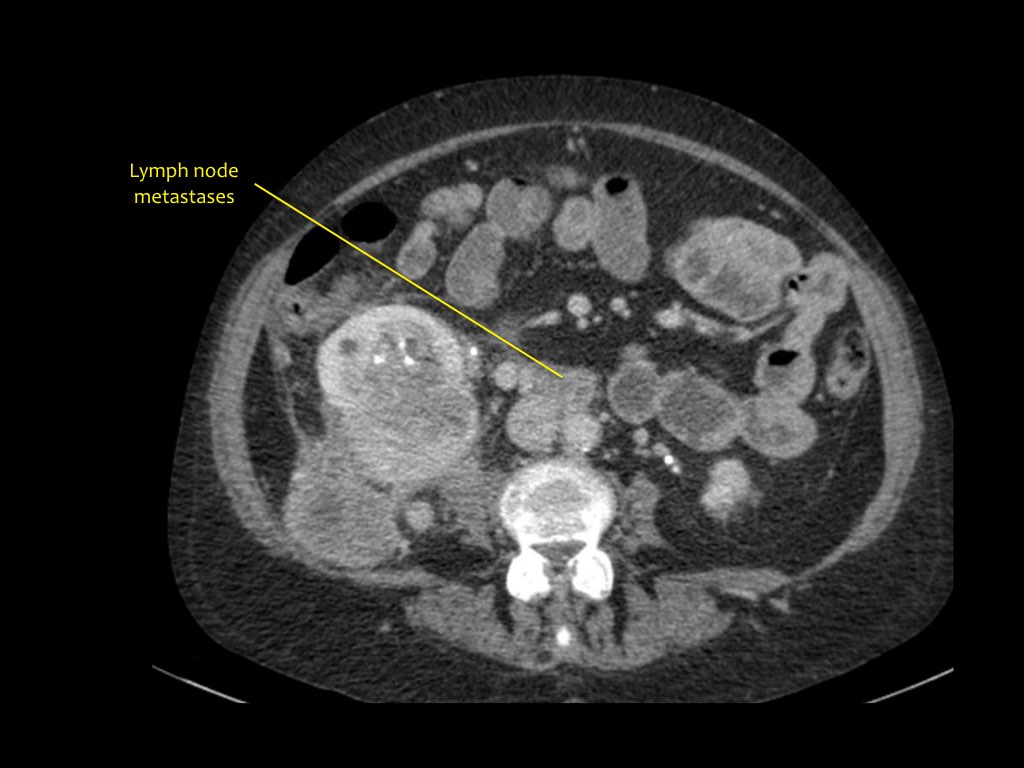

Di căn

Tổn thương xâm lấn ở cực dưới thận phải, phát triển đáng kể sau sáu tháng, kèm theo hạch bạch huyết lan rộng. Đây được xác định là di căn của ung thư phổi.

Các khối u ác tính nguyên phát thường di căn đến thận nhất bao gồm ung thư phổi, ung thư vú, các khối u đường tiêu hóa và u hắc tố (melanoma).

Di căn thận thường xuất hiện muộn trong tiến trình của một bệnh ác tính đã biết, như một phần của bệnh lan rộng toàn thân.

Trong một số ít trường hợp, di căn thận có thể biểu hiện dưới dạng một tổn thương đơn độc và khó phân biệt với ung thư biểu mô tế bào thận.

Di căn thận thường có kích thước nhỏ, đa ổ và hai bên, với hình thái phát triển xâm lấn.

Có một tổn thương di căn ở thận trái và nhiều tổn thương di căn hạch bạch huyết (mũi tên).

Nếu đây là biểu hiện duy nhất, sẽ rất khó để phân biệt với ung thư biểu mô tế bào thận có di căn hạch bạch huyết.